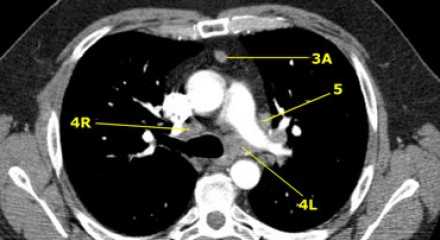

4L. Левые нижние паратрахеальные лимфатические узлы

4L узлы расположенные слева от левой стенки трахеи, между горизонтальными линиями проведенными касательно верхней стенке дуги аорты и линией проходящей через левый главный бронх на уровне верхнего края верхнедолевого бронха. Они включают паратрахеальные узлы расположенные кнутри от артериальной связки.

Узлы 5 группы (аортопульмонального окна) расположены кнаружи от артериальной связки.

На левом изображении над уровнем легочного ствола представлены нижние паратрахеальные узлы слева и справа, так же здесь представлены узлы 3 и 5 групп.

Изображение слева выше уровня карины. Слева от трахеи 4L узлы. Обратите внимание что они расположены между легочным стволом и аортой, но не в аортопульмональном окне, потому что они лежат медиальнее артериальной связки. Лимфатические узлы латеральнее легочного ствола относятся к 5 группе.

- 5. Субаортальные лимфатические узлы - Субаортальное или аортопульмональное окно расположено кнаружи от артериальной связки и проксимальнее первой ветви левой легочной артерии и лежит в пределах медиастинальной плевры.